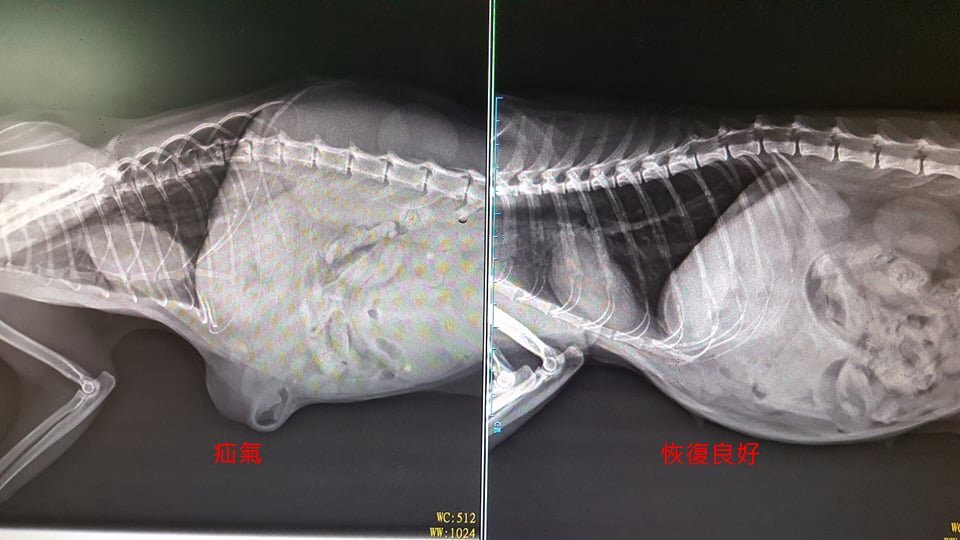

主題: 貢寮疝氣三花貓 申請者姓名: 臺北市支持流浪貓絕育計劃協會 花色: 申請日期: 2019-08-04 18:43:40 申請者部落格: 申請者臉書網址: 所在縣市/合作醫院: 台北市/欣旺動物醫院 治療費用: 21200元 需求人數: 48人 已結案 (2024-05-31 18:29:04) 報名人員: Shannon(已付款)、amberkuyin(已付款)、豬妞妞(已付款)、佳茵(已付款)、花語韶光(已付款)、Wennie Tseng(已付款)、S、S x2(已付款)、Pearl Hsu(已付款)、Chi(已付款)、AARON CHI(已付款)、Kimmie Huang(已付款)、Feliz(已付款)、丫丫 x3(已付款)、Soflen x6(已付款)、庭(已付款)、Eric.Chang(已付款)、簡佑銘(已付款)、eason7225(已付款)、LU(已付款)、GarField Lin(已付款)、Nicole Hsiao(已付款)、Mya(已付款)、左梅梅 x6(已付款)、hsinkai0407 x2(已付款)、ANRONG WANG x3(已付款)、Nicky Huang x3(已付款)、Nina Chang x3(已付款)、nicole chen(已付款)、 候補人員: 動物病情說明: 協會接獲許多貢寮地區通報結紮的案件

送至醫院X光檢查

確診腹部疝氣

需手術縫合

術後休養兩周後拆線

狀況良好也圓潤很多